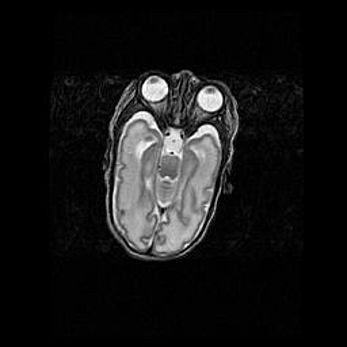

Мальформация Денди-Уокера. Киста задней черепной ямки.

Агенезия мозолистого тела.

Возраст: 2,5 месяца

Вес: 2420 г

Пол: женский

Окружность головы: 37 см

Срок гестации: 32 недели

Мальформация Денди—Уокера — редкий вид патологии ЦНС, представляющий собой врожденный порок развития каудального отдела ствола и червя мозжечка, ведущий к неполному раскрытию срединной (Мажанди) и латеральных (Лушка) апертур IV желудочка мозга. Для этогно синдрома характерна триада симптомов: гипотрофия червя мозжечка и/или полушарий мозжечка, кисты задней черепной ямки, гидроцефалия различной степени. В 70% случаев порок сочетается и с другими аномалиями головного мозга, в частности с агенезией мозолистого тела.